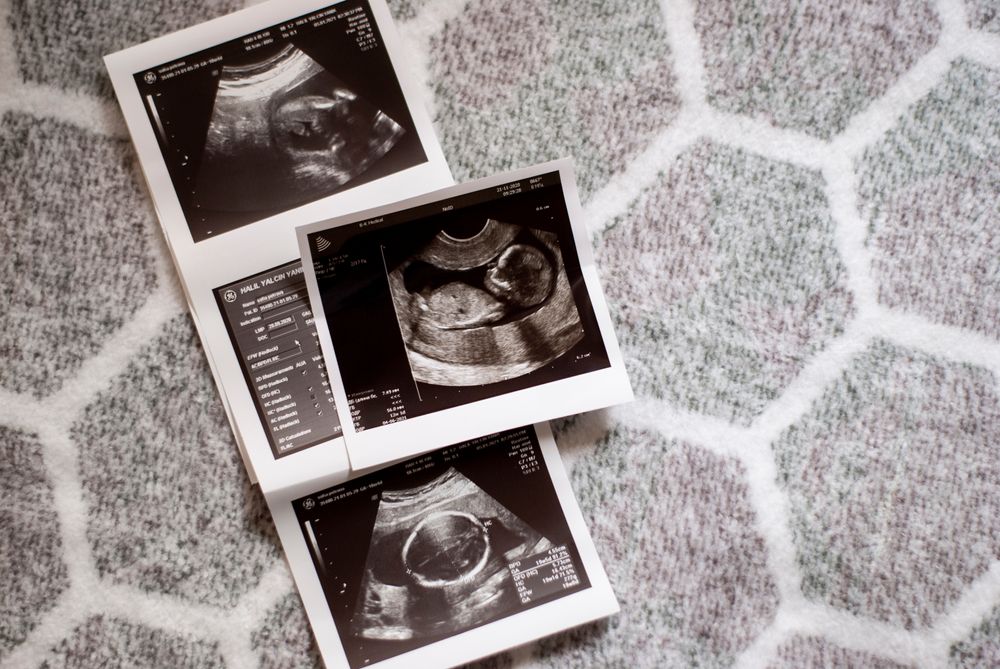

Trong suốt hành trình mang thai, việc theo dõi sự phát triển của em bé luôn được chú trọng. Các chỉ số thai nhi theo tuần được thu thập thông qua hình thức siêu âm thai là những thông số phản ánh sự phát triển của thai nhi về kích thước, cân nặng, hình thái… Dựa vào các chỉ số này, bác sĩ có thể đánh giá được sức khỏe của thai nhi và kịp thời phát hiện những bất thường nếu có. Bài viết sau, Hello Bacsi sẽ cùng bạn tìm hiểu chi tiết về chủ đề chỉ số thai nhi theo tuần để hiểu thêm về các mốc phát triển của thiên thần nhỏ.

Một số chỉ số thai nhi theo tuần quan trọng thường được thể hiện trên phiếu siêu âm thai mà mẹ cần biết là:

- GA (Gestational age): Tuổi thai tính từ ngày đầu của chu kỳ kinh cuối.

- CRL (Crown rump length): Chiều dài đầu mông. Thông thường, trong 3 tháng đầu thai kỳ, thai nhi sẽ ở tư thế hơi co lại nên rất khó đo chiều dài đầu – chân, do đó các bác sĩ thường sẽ đo chiều dài đầu mông. Từ 14 trở đi, không còn sử dụng chỉ số chiều dài đầu mông để đánh giá sự phát triển của em bé, mà thay vào đó là các thông số đầu, bụng, đùi.

- BPD (Biparietal diameter): Đường kính lưỡng đỉnh, là đường kính lớn nhất ở mặt cắt vòng đầu bé.

- FL (Femur length): Chiều dài xương đùi.

- EFW (Estimated fetal weight): Cân nặng thai nhi ước tính.

- GSD (Gestational sac diameter): Đường kính túi thai được đo trong những tuần đầu của thai kỳ.

- HC (Head circumference): Chu vi đầu.

- AC (Abdominal circumference): Chu vi vòng bụng.

- AF (Amniotic fluid): Nước ối.

- AFI (Amniotic fluid index): Chỉ số nước ối.